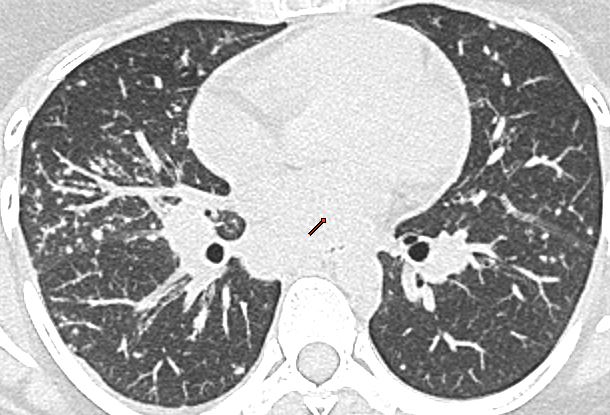

Contrast enhanced CT scan of thorax, showing multiple relatively symmetric well defined mildly enlarged non-necrotic nodes in the paratracheal and aortopulmonary regions.

The common differential diagnosis includes:

a. Tuberculosis: The presence of necrosis within the node favors TB as the diagnosis. However TB can also present with non-necrotic nodes; so the absence of necrosis is not as useful a feature.

b. Sarcoidosis: It usually presents as bilateral symmetric hilar, paratracheal, and subcarinal adenopathy, without bulky prevascular nodes. Lung nodules in perihilar, perilymphatic, and perifissural distribution are diagnostic.

c. Lymphoma: It usually presents with enlarged confluent prevascular adenopathy.

Case courtesy of A.Prof Frank Gaillard, <ahref=”https://radiopaedia.org/”>Radiopaedia.org</a>. From the case <a href=”https://radiopaedia.org/cases/8655″>rID: 8655</a>

d. Metastasis: Metastasis is a great mimicker, and should always be a differential in older patients.